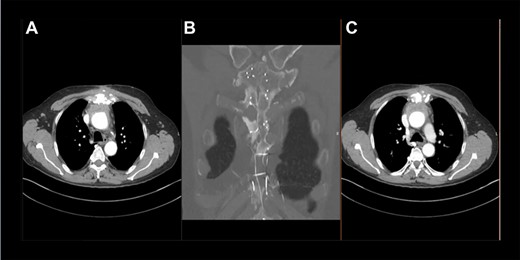

At almost 6 years after the initial surgery, the patient was transferred to our unit with a chronic sternal fistula. The computed tomography (CT) scan showed almost complete destruction of the manubrium sterni on the left side, a fistula path into the anterior mediastinum and an abscess collection around the ascending aorta (Fig. 1). The echocardiography ruled out any significant valve regurgitation or stenosis, endocarditis or aortic root abscess. Pseudomonas aeruginosa was cultivated from the fistula.

Preoperative thoracic CT scan; (A) image indicates the sternal defect caused by osteomyelitis and the infected hematoma surrounding the native aortic arch; (B) topogram indicating the sternal defect caused by osteomyelitis in coronary sectional plane; (C) image indicates the sternal defect caused by osteomyelitis and the infected hematoma surrounding the aortic prosthesis.